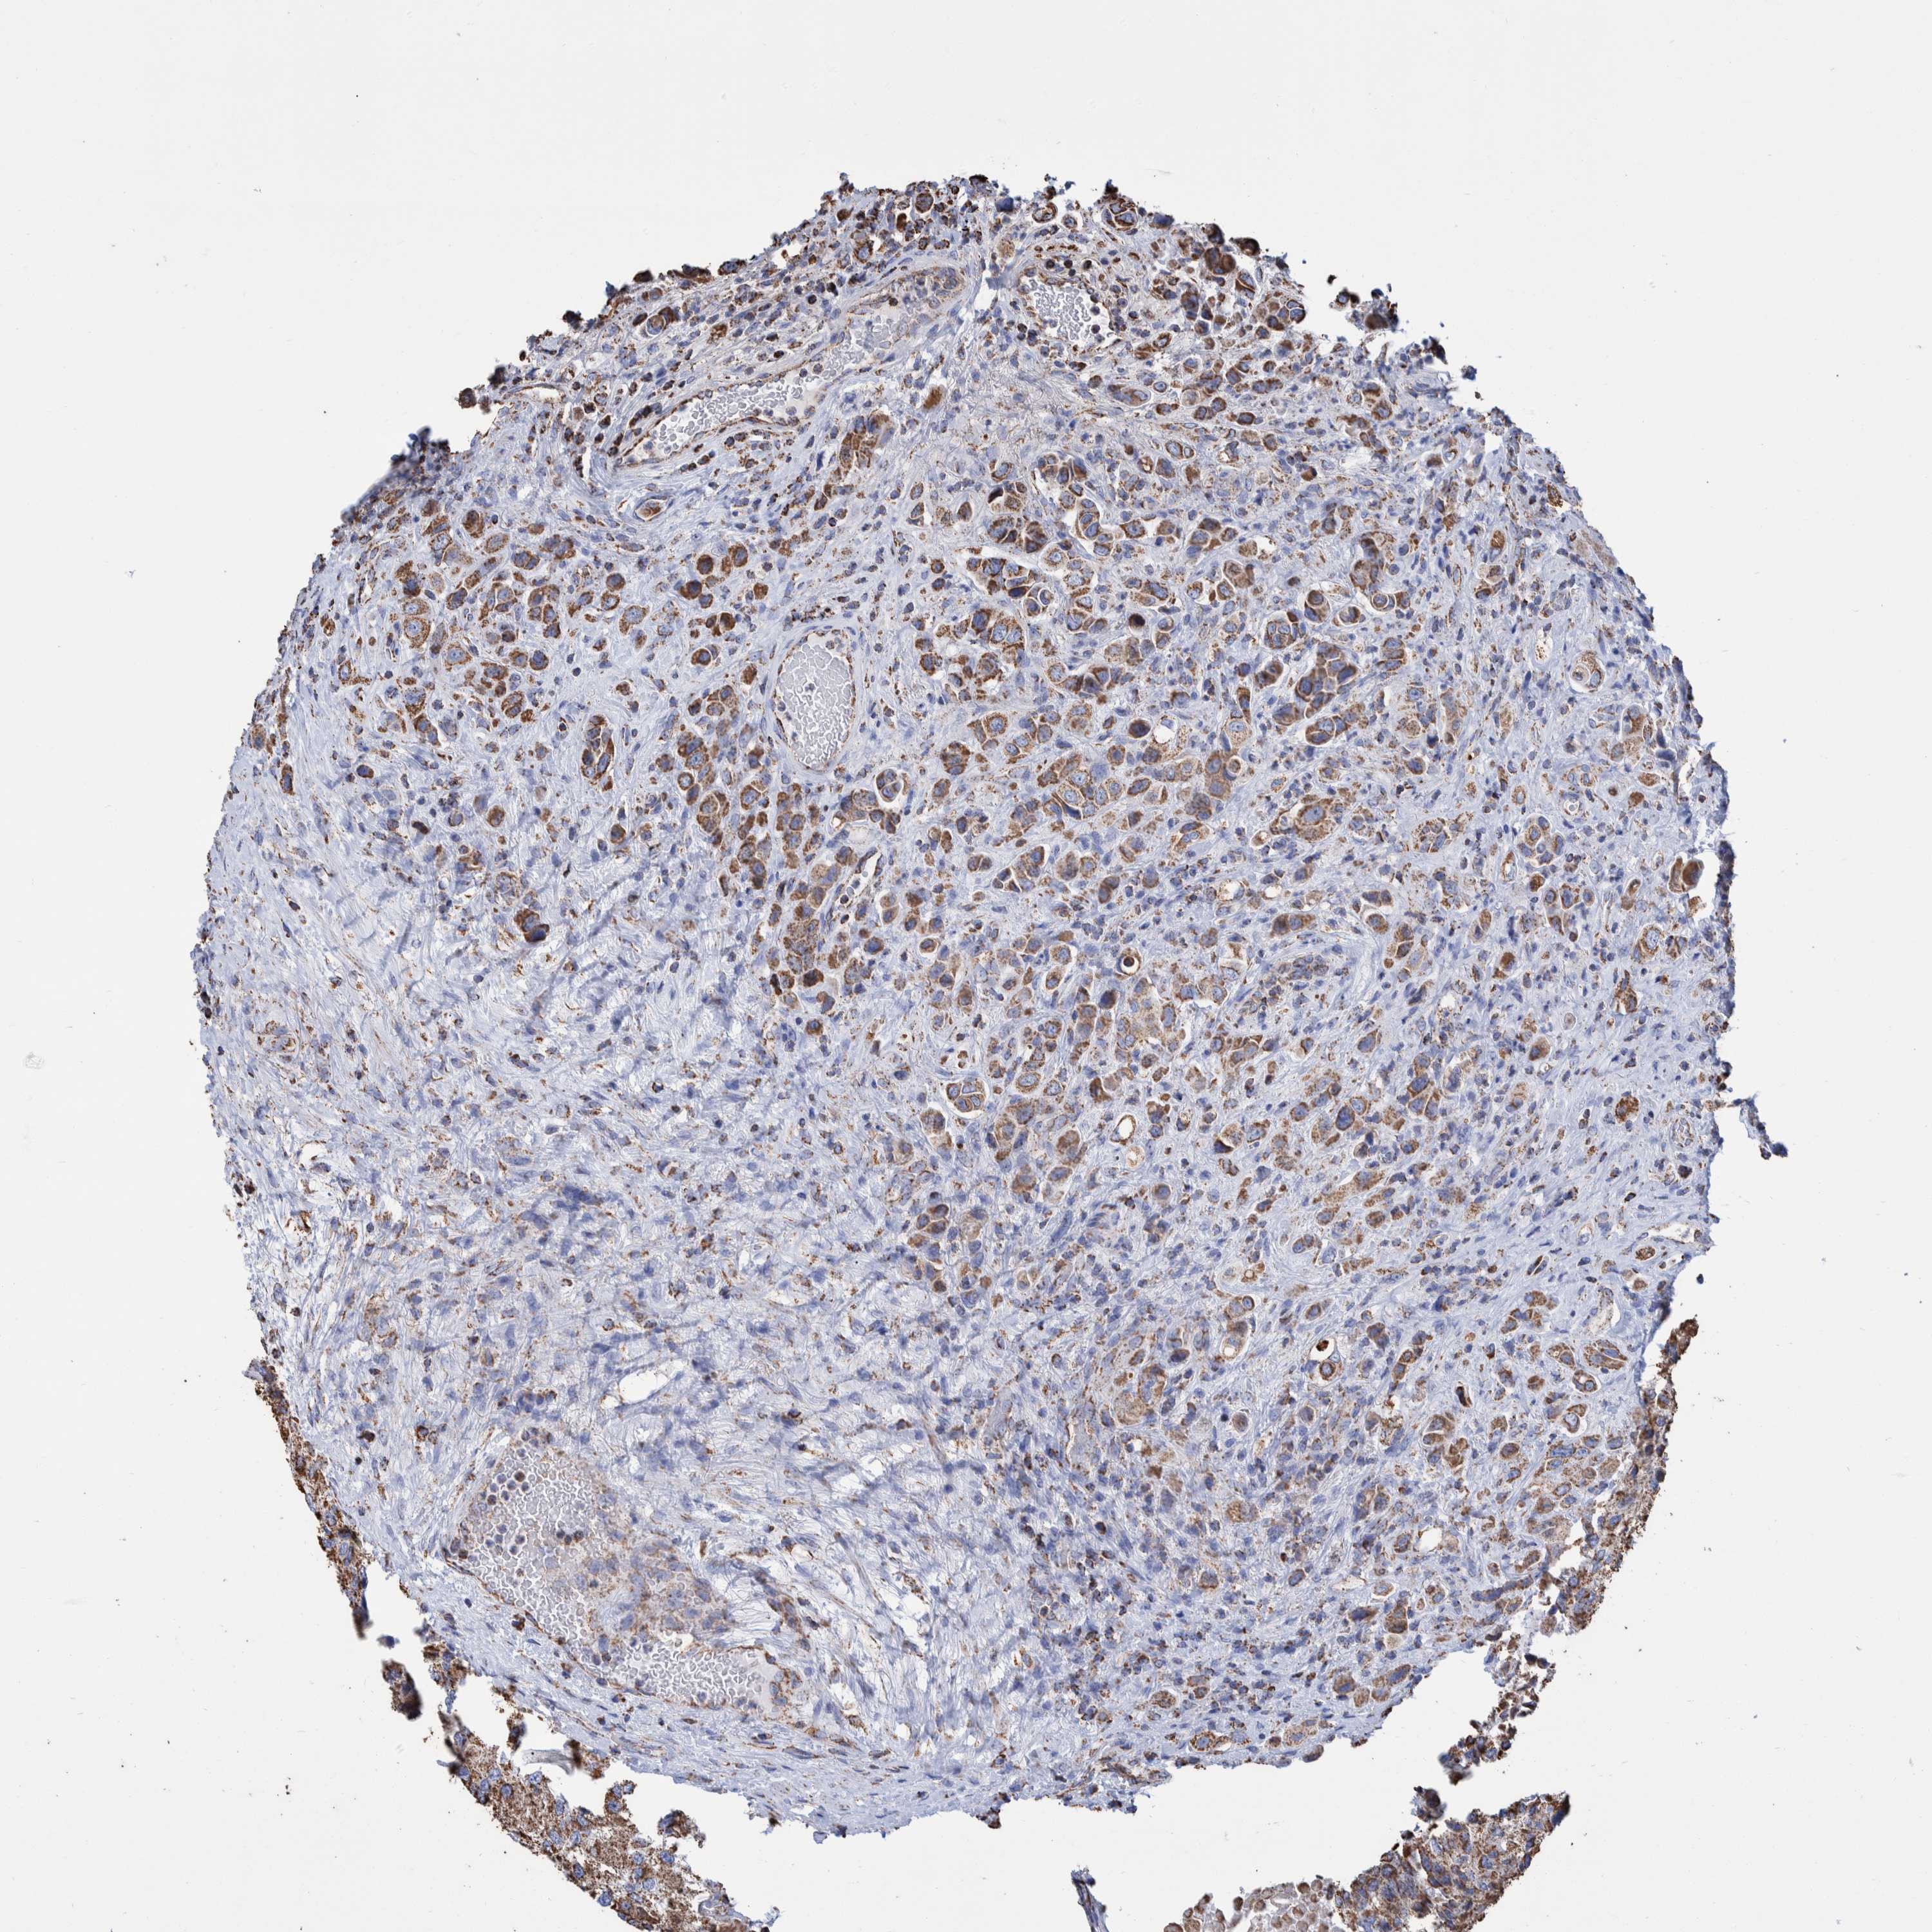

UROTHELIAL CANCER - Protein expressioni

A mouse-over function shows sample information and annotation data. Click on an image to view it in a full screen mode. Samples can be filtered based on level of antibody staining by selecting one or several of the following categories: high, medium, low and not detected. The assay and annotation is described here.

Note that samples used for immunohistochemistry by the Human Protein Atlas do not correspond to samples in the TCGA dataset.

Antibody stainingi

Antibody staining in the annotated cell types in the current human tissue is reported as not detected, low, medium, or high, based on conventional immunohistochemistry profiling in selected tissues. This score is based on the combination of the staining intensity and fraction of stained cells.

Each image is clickable and will lead to virtual microscopy that enables deeper exploration of all samples and also displays staining intensity scores, fraction scores and subcellular localization as well as patient and tissue information for each sample.

Antibody HPA023288

Staining

High

Medium

Low

Not detected

Intensity

Strong

Moderate

Weak

Negative

Quantity

>75%

75%-25%

<25%

None

Location

Nuclear

Cytoplasmic/membranous

Cytoplasmic/membranous,nuclear

Urothelial carcinoma, Low grade

Urothelial carcinoma, High grade